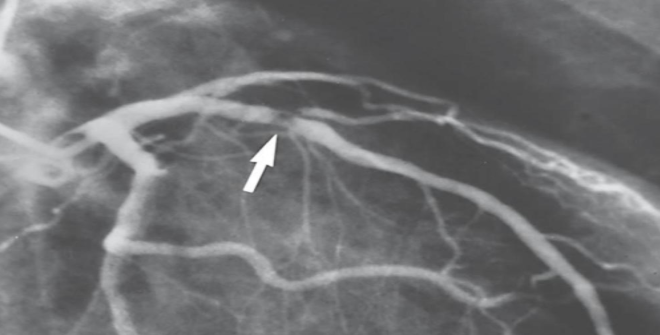

what is this?

active hyperemia in asd